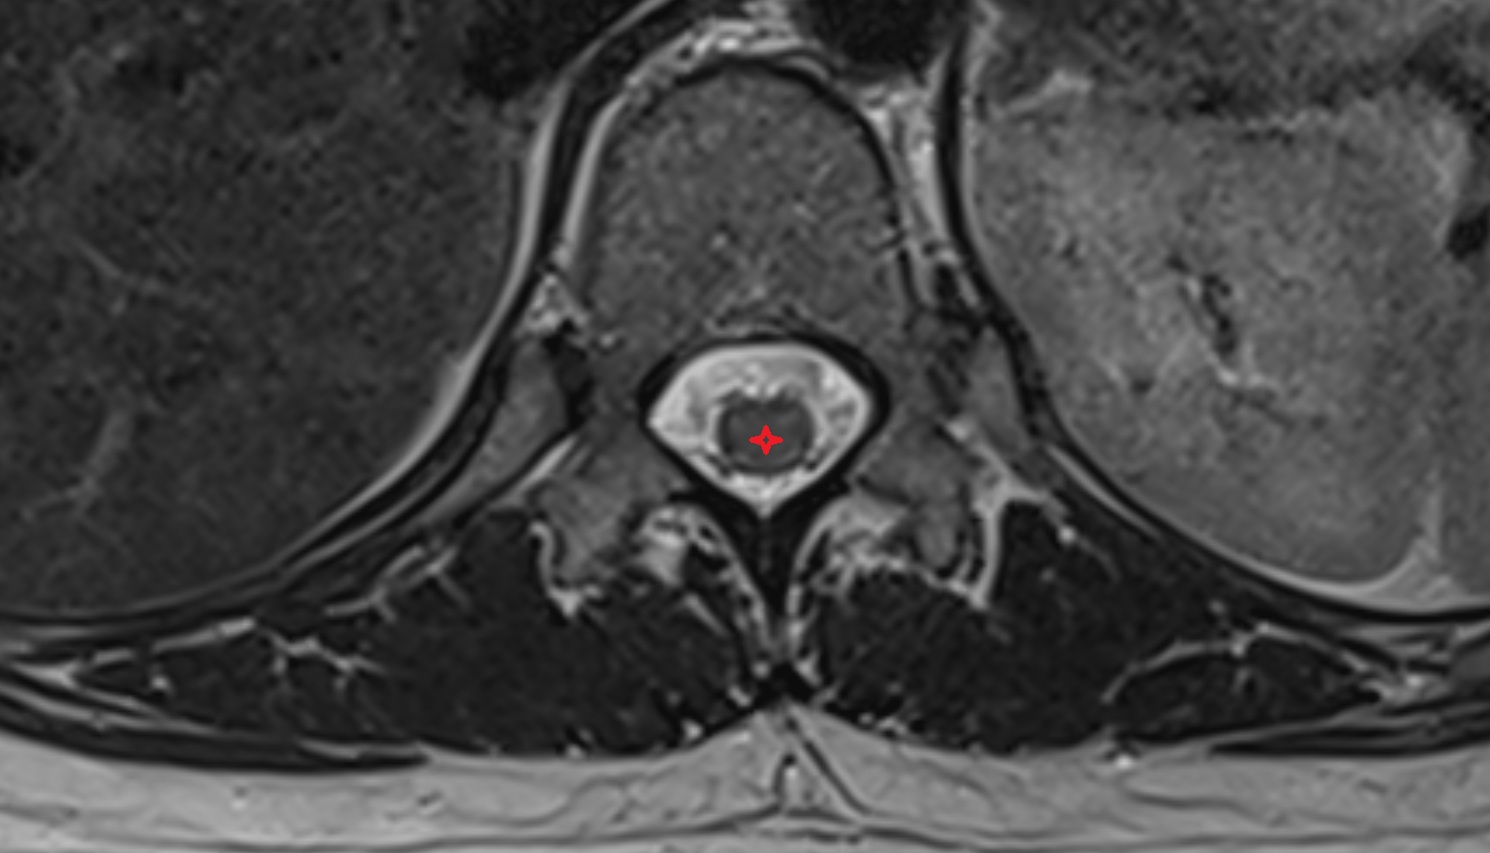

- Peripheral zone of prostate

- Anterior Fibromuscular Stroma of prostate

- Central zone of prostate

- Transitional zone of prostate